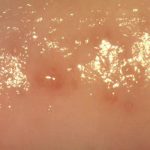

Провоцируется генитальный герпес (фото 1) вирусом первого или второго типа. У большинства больных симптомы генитального герпеса спровоцированы проникновением в организм вируса второго типа. Признаки генитального герпеса локализованы непосредственно в области половых органов. Внешне герпетическая сыпь выглядит выступающими над поверхностью кожи пузырьками, наполненными прозрачной жидкостью.

Вокруг сыпи появляются гиперемированные участки с неровными краями, а сами пузырьки болезненные при прикосновении. Пожелтение содержимого пузырьков говорит о скором их вскрытии. В последней стадии генитального герпеса пузырьки лопаются и превращаются в ранки, которые заживают через несколько дней.

Выглядит генитальный герпес как островки сыпи, в центре которых расположены скученные пузырьки, наполненные жидкостью, и немного поодаль, на периферии расположены одиночные высыпания. Все они находятся на гиперемированном отечном кожном покрове и болезненны при прикосновении. В своем развитии герпес проходит все стадии – высыпания, созревания и разрешения болезни, когда пузырьки превращаются в корки и заживают.